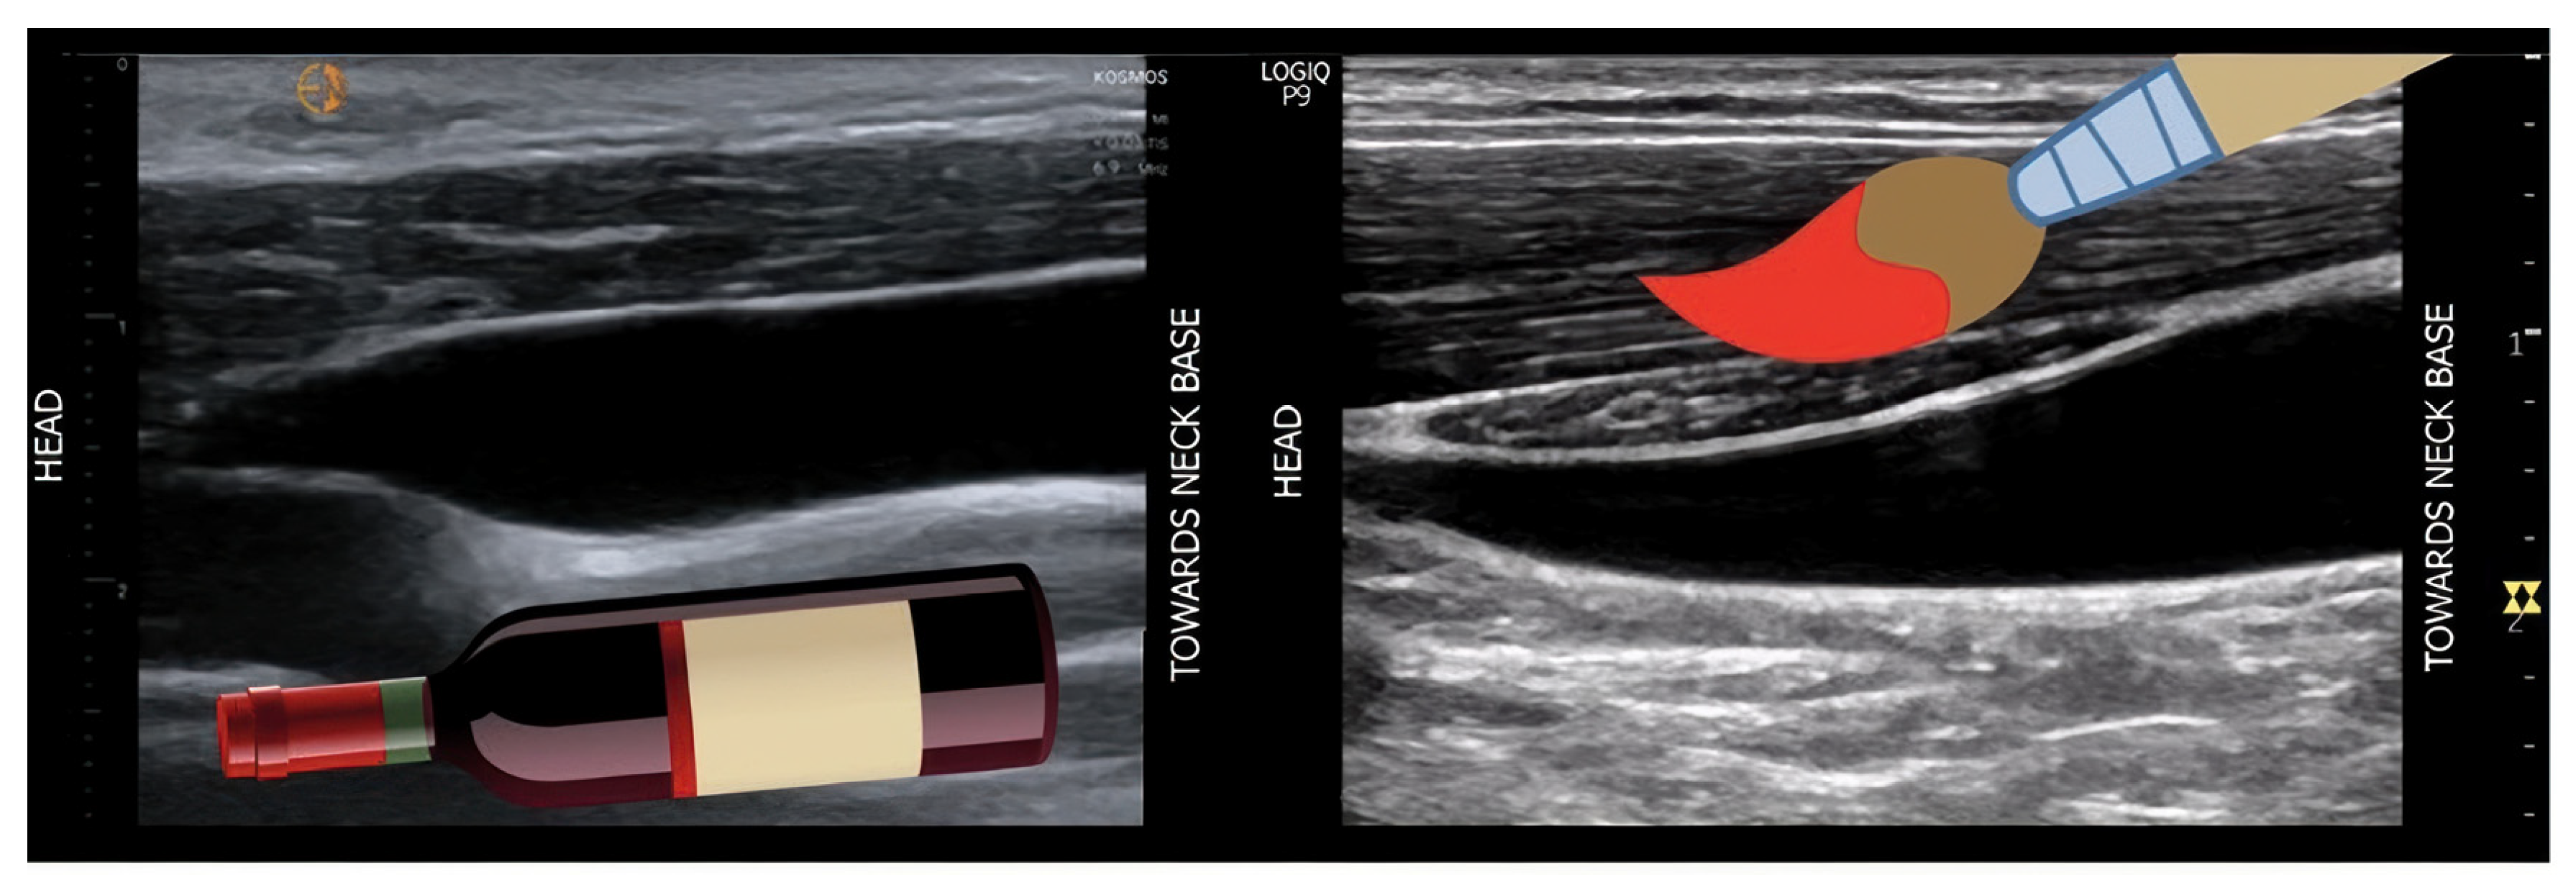

- Increased Pulsatility (Pulsatile Waveform): A pulsatile portal venous flow occurs when there is a significant difference between peak systolic and end-diastolic velocities. This is due to abnormal transmission of pressure through the hepatic sinusoids, often caused by conditions like tricuspid regurgitation, right-sided heart failure (CHF), or arteriovenous shunting (as seen in cirrhosis or hereditary haemorrhagic telangiectasia (Figure 9A) [105]. Pulsatility can be differentiated clinically, with right-sided CHF and tricuspid regurgitation identifiable through the hepatic venous waveform and grayscale US showing dilated hepatic veins, unlike in cirrhosis, where hepatic veins are compressed.

- Hepatofugal (Retrograde) Flow: Hepatofugal flow happens when the pressure in the portal vein exceeds that of the liver, causing flow to reverse and appear below the baseline. This is another indicator of portal hypertension, which can be caused by various conditions, including cirrhosis, right-sided heart failure and other portal vein obstructions [107] (Figure 9).Figure 9. (A) Increased pulsatility due to arteriovenous shunting in a case of hereditary haemorrhagic telangiectasia; (B) Reduced Portal Flow in a case of cirrhosis (C) Hepatofugal Flow of Portal Vein is a late sign of Portal Hypertension. It happens when the pressure in the portal vein exceeds that of the liver, causing flow to reverse and appear below the baseline. This is another indicator of portal hypertension, which can be caused by various conditions, including cirrhosis, right-sided heart failure and other portal vein obstructions.Figure 9. (A) Increased pulsatility due to arteriovenous shunting in a case of hereditary haemorrhagic telangiectasia; (B) Reduced Portal Flow in a case of cirrhosis (C) Hepatofugal Flow of Portal Vein is a late sign of Portal Hypertension. It happens when the pressure in the portal vein exceeds that of the liver, causing flow to reverse and appear below the baseline. This is another indicator of portal hypertension, which can be caused by various conditions, including cirrhosis, right-sided heart failure and other portal vein obstructions.